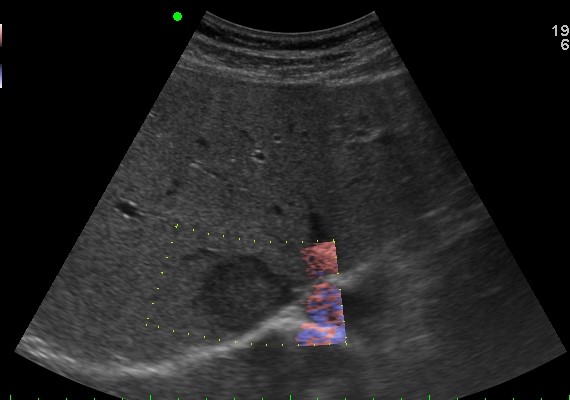

GB & BD ) CCC |

2019.05.11 мЎ°нҡҢмҲҳ: 231 |